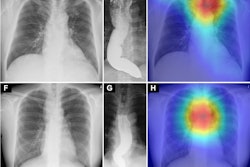

An example that features an AI-generated report that identified “scattered pulmonary granulomatous calcifications.” In the first session, three of five readers specifically reported the presence of a nodule. Following the introduction of the AI-generated report, only one reader maintained the specific mention of a nodule, whereas the other four readers adapted their reports to include the AI-suggested terminology of “granulomatous calcifications.” AP = anterior-posterior. Image and caption courtesy of RSNA.